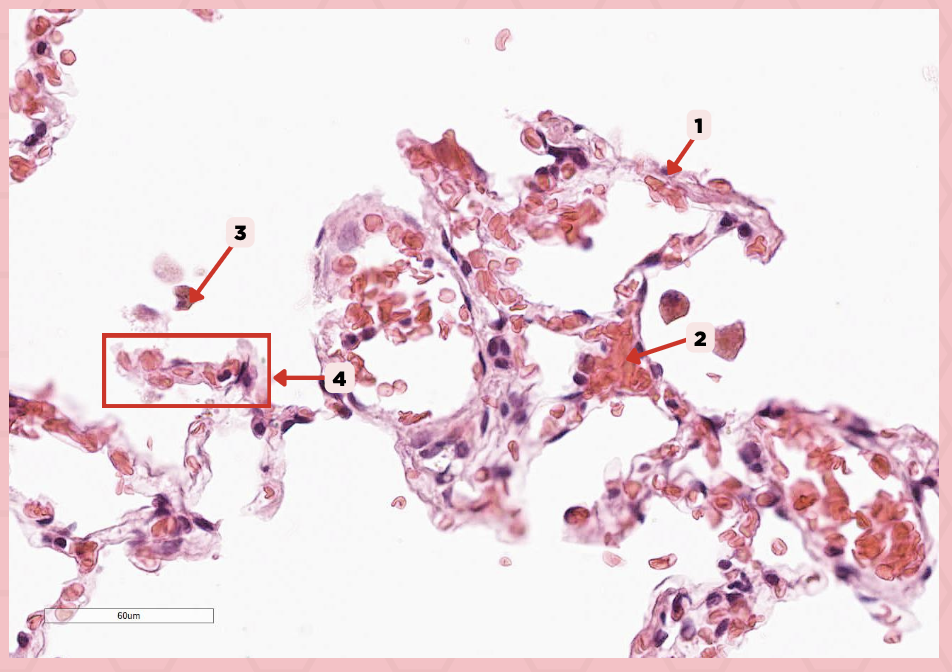

Type 1 and Type 2 Alveolar Cells

What are the 2 cell types for alveoli?

Simple squamous epithelium

What kind of epithelium are these alveolar cells?

Interalveolar septum

Identify the structure labeled as 1.

Type I alveolar cell

Identify the structure labeled as 2.

Type II alveolar cell

Identify the structure labeled as 3.

Pulmonary Alveolar Macrophages (Dust Cells)

Identify the structure labeled as 4.

Pulmonary Alveolar Macrophages (Dust Cells)

What are the most numerous cells inside the alveoli?

Pneumocyte Type I

Which of the following labeled structures covers 95% of the alveolar surface?

Type I alveolar cell

Identify the structure labeled as 1.

Type II alveolar cell

Identify the structure labeled as 2.

Pulmonary Alveolar Macrophages (Dust Cells)

Identify the structure labeled as 3.

Endothelial Cells

Identify the structure labeled as 4.